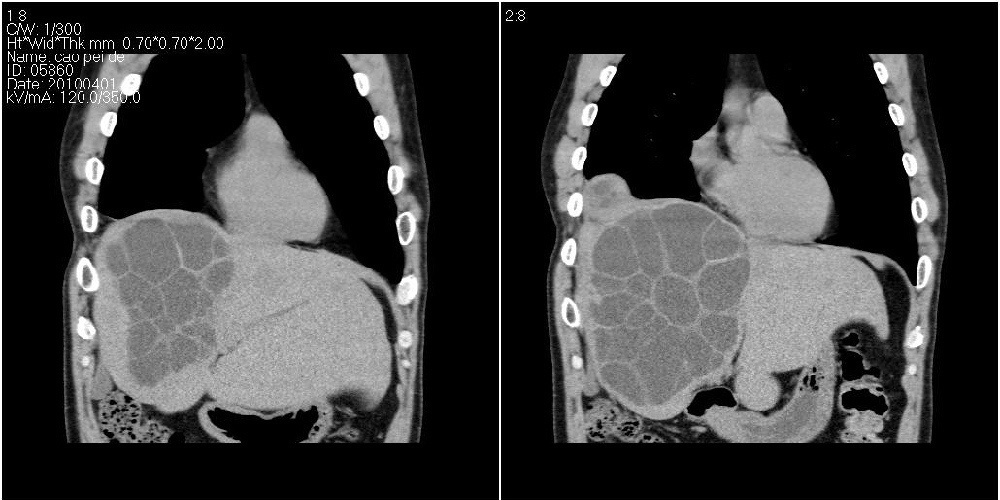

该患者70岁男性,手术后10年,现复查。2008年6月份本人曾经发过一极其类似的病例,只是部位略有差异。

多囊肝

肝脏多房性包虫囊肿

水上浮莲征,肝包虫囊肿。

肝脏及右侧胸腔包虫病。

大囊套小囊!肝脏多房性包虫囊肿